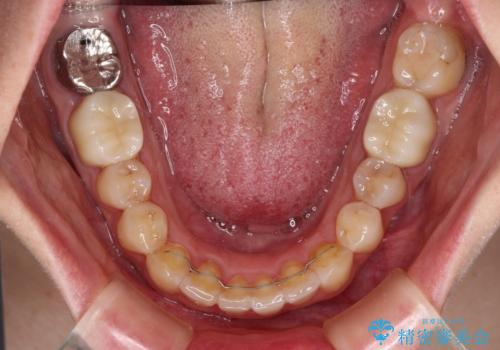

- 前歯のデコボコと奥歯の虫歯を気にして来院された患者様です。

主に下顎歯列全体の後方移動とIPR(歯と歯の間を削る)によってデコボコが解消するように設計し、インビザラインにより治療を行うこととしました。

矯正治療後半に下顎左右奥歯をセラミッククラウンにて補綴し、その後インビザラインによる歯列の仕上げを行うこととしました。

下顎前歯の叢生が速やかに改善されたため、1年3か月で治療を終えることができました。

下顎前歯は後戻りを起こしやすいため、舌側を細いワイヤーで固定することで後戻り対策を行っています。